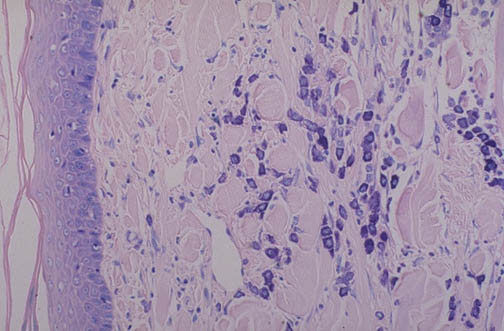

| A giemsa stain demonstrates numerous mast cells in the dermis of the skin. The mast cells contain numerous purple granules; the granules contain many substances, including vasoactive amines such as histamine, which are released upon activation and degranulation of the mast cells to cause immune responses. The granules demonstrate the property of "metachromasia" (change in color) because the dye is blue but the granule color is purple. |